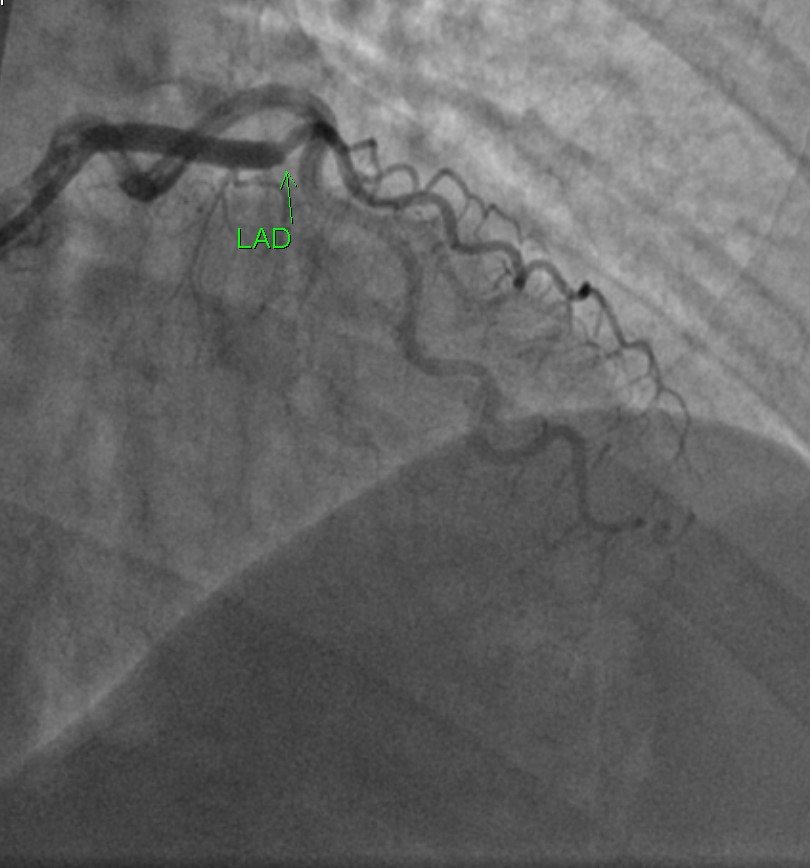

The patient bypassed the ED and went directly to angiogram:

![]() |

| After stenting, there is good flow in the LAD |